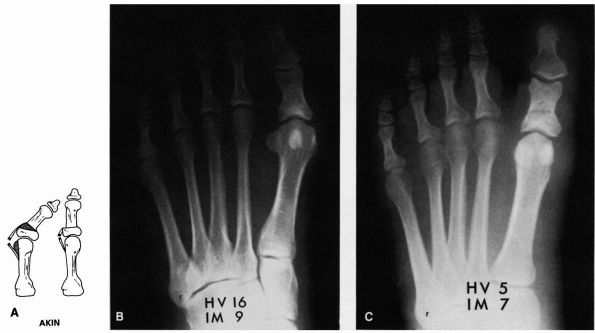

![]() |

FIGURE 21-8. Akin procedure. (A) The medial eminence is excised, and a medially based wedge of bone is removed from the proximal phalanx. Preoperative (B) and postoperative (C) radiographs demonstrating an Akin procedure.

lateral side is due to a deformity at the level of the interphalangeal

This deformity of the toe can be corrected by a closing-wedge osteotomy

of the base of the proximal phalanx, also called the Akin procedure (Figure 21-8).